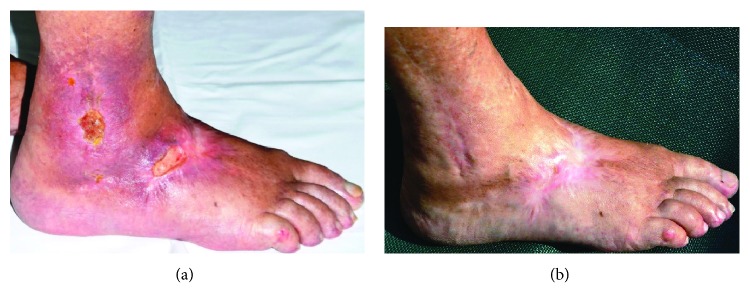

The ability to produce cold plasma at atmospheric pressure conditions was the basis for the rapid growth of plasma-related application areas in biomedicine. Plasma comprises a multitude of active components such as charged particles, electric current, UV radiation, and reactive gas species which can act synergistically. Anti-itch, antimicrobial, anti-inflammatory, tissue-stimulating, blood flow-enhancing, and proapoptotic effects were demonstrated in in vivo and in vitro experiments, and until now, no resistance of pathogens against plasma treatment was observed. The combination of the different active agents and their broad range of positive effects on various diseases, especially easily accessible skin diseases, renders plasma quite attractive for applications in medicine. For medical applications, two different types of cold plasma appear suitable: indirect (plasma jet) and direct (dielectric barrier discharge-DBD) plasma sources. The DBD device PlasmaDerm® VU-2010 (CINOGY Technologies GmbH), the atmospheric pressure plasma jet (APPJ) kINPen® MED (INP Greifswald/neoplas tools GmbH), and the SteriPlas (Adtec Ltd., London, United Kingdom) are CE-certified as a medical product to treat chronic wounds in humans and showed efficacy and a good tolerability. Recently, the use of plasma in cancer research and oncology is of particular interest. Plasma has been shown to induce proapoptotic effects more efficiently in tumor cells compared with the benign counterparts, leads to cellular senescence, and-as shown in vivo-reduces skin tumors. To this end, a world-wide first Leibniz professorship for plasmabiotechnology in dermatology has been introduced to establish a scientific network for the investigation of the efficacy and safety of cold atmospheric plasma in dermatooncology. Hence, plasma medicine especially in dermatology holds great promise.